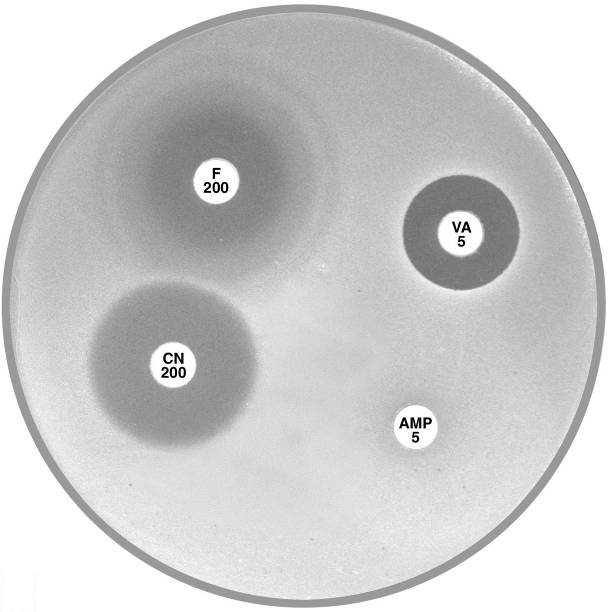

Plate 12.1.C Enterococcus faecium and nitrofurantoin The hazy edged zone of inhibition around nitrofurantoin and no zone of inhibition around ampicillin is characteristic of E. faecium. |